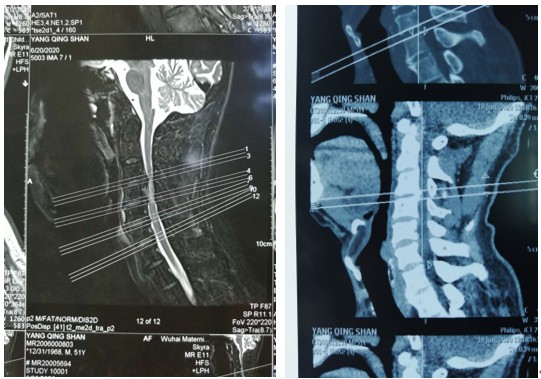

近日,杨先生前晚同好友畅饮,第二日起床时一不小心扭了脖子,据杨先生说:“就是一扭头觉得闪了一下”当下感觉双臂麻木、疼痛、使不上劲儿,双腿也是麻木无力。家人以为“酒精伤了神经”将杨先生送往乌海市人民医院神经内科进行诊治,神经内科副主任医师冯兴丽接诊,发现杨先生并非神经损伤症状,反而像是椎管受损,便立即将杨先生交由有“钢铁脊梁”之称的人民医院骨科脊柱外科团队进行诊治。“钢铁脊梁”组组长主任医师刘涛在结合杨先生CT检查结果后明确诊断为“颈椎椎管狭窄合并颈脊髓损伤”,正是杨先生“扭头闪了一下”闪伤了“脊梁骨”。

确定病因后立刻为杨先生安排了手术,市人民医院“钢铁脊梁”脊柱外科组组长长刘涛、组员副主任医师张运动、住院医师张治河、住院医师王继龙四人齐上阵,为杨先生实施“颈椎后路单开门椎管扩大减压成形术”术后由副主任医师张运动负责管床,杨先生上下肢疼痛麻木感立刻减轻,次日双侧上下肢活动恢复,也可下地行走。